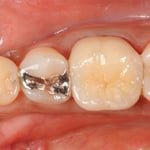

”穿孔”とは、簡単に言えば、歯の中に異常な”穴”が開いていることです。通常なら明らかに抜歯と診断されても不思議ではない症例ですが、時間をかけて修復しました。奥は他院で行ったインプラントですが、問題なく機能しています。

大臼歯の近心根の遠心壁に大きな穿孔が生じていた症例です。体格の良い男性でした。CTによる読影でも、大きな透過像が確認されます。この症例は、チタンメッシュとスーパーボンドを用いて修復しました。

CTでは、頬側の骨が破壊されていないことがわかります。おそらく、治療できるギリギリの時期であったかもしれません。穿孔封鎖後、遠心根も近心根も清掃拡大し、バイオセラミックスにて根尖を封鎖し、グラスファイバーにて築造。上部構造は、メタルのクッション性、メタルマージンの補綴物によるフェルール(帯環)効果を考え、P.F.M.C.としました。